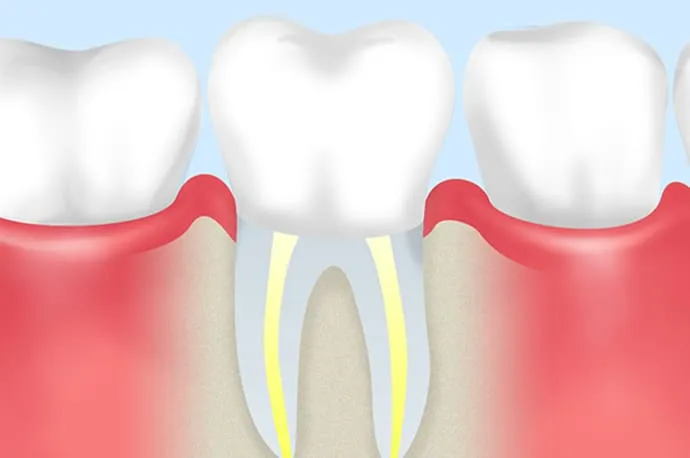

根管充填と土台作り

再来院時に問題がなければ、根管内に防腐剤の詰め物を行います(根管充填)。その後、感染を防ぐため、歯と強力に接着するレジンなどの材料で上からフタをし、歯の土台を作ります(築造)。

その後は、できるだけ早めに型採りを行い、仮歯や最終的な被せ物を作製していく流れとなります。

当院では、根管治療後の歯には基本的に被せ物での修復をご提案しています。詰め物と比べると、健康な歯の部分を少し削る必要がありますが、その分歯全体をしっかり補強できます。実際、根管治療後に抜歯になってしまった歯の多くは、被せ物をしていなかったケースが多いというデータもあります。

根管治療で感染をしっかりコントロールしたうえで、精度の高い被せ物で修復すれば、予後は十分に安定しており、あまり心配する必要はありません。